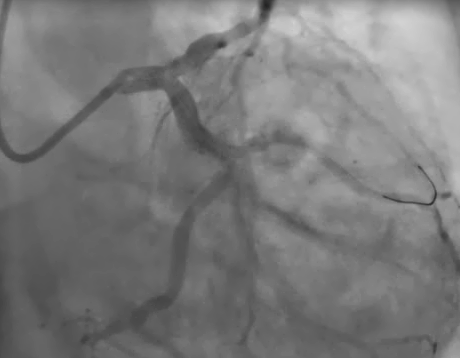

FFR of LAD

• The COMETTM FFR wire was delivered down the LAD and gives an FFR value of 0.83

• No stents placed

FFR COMET fig 2

FFR value of 0.83